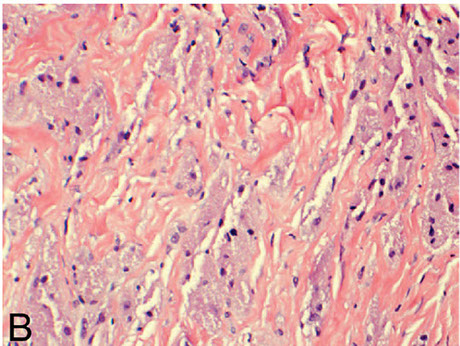

Elastofibroma

Chenille bodies in elastofibroma